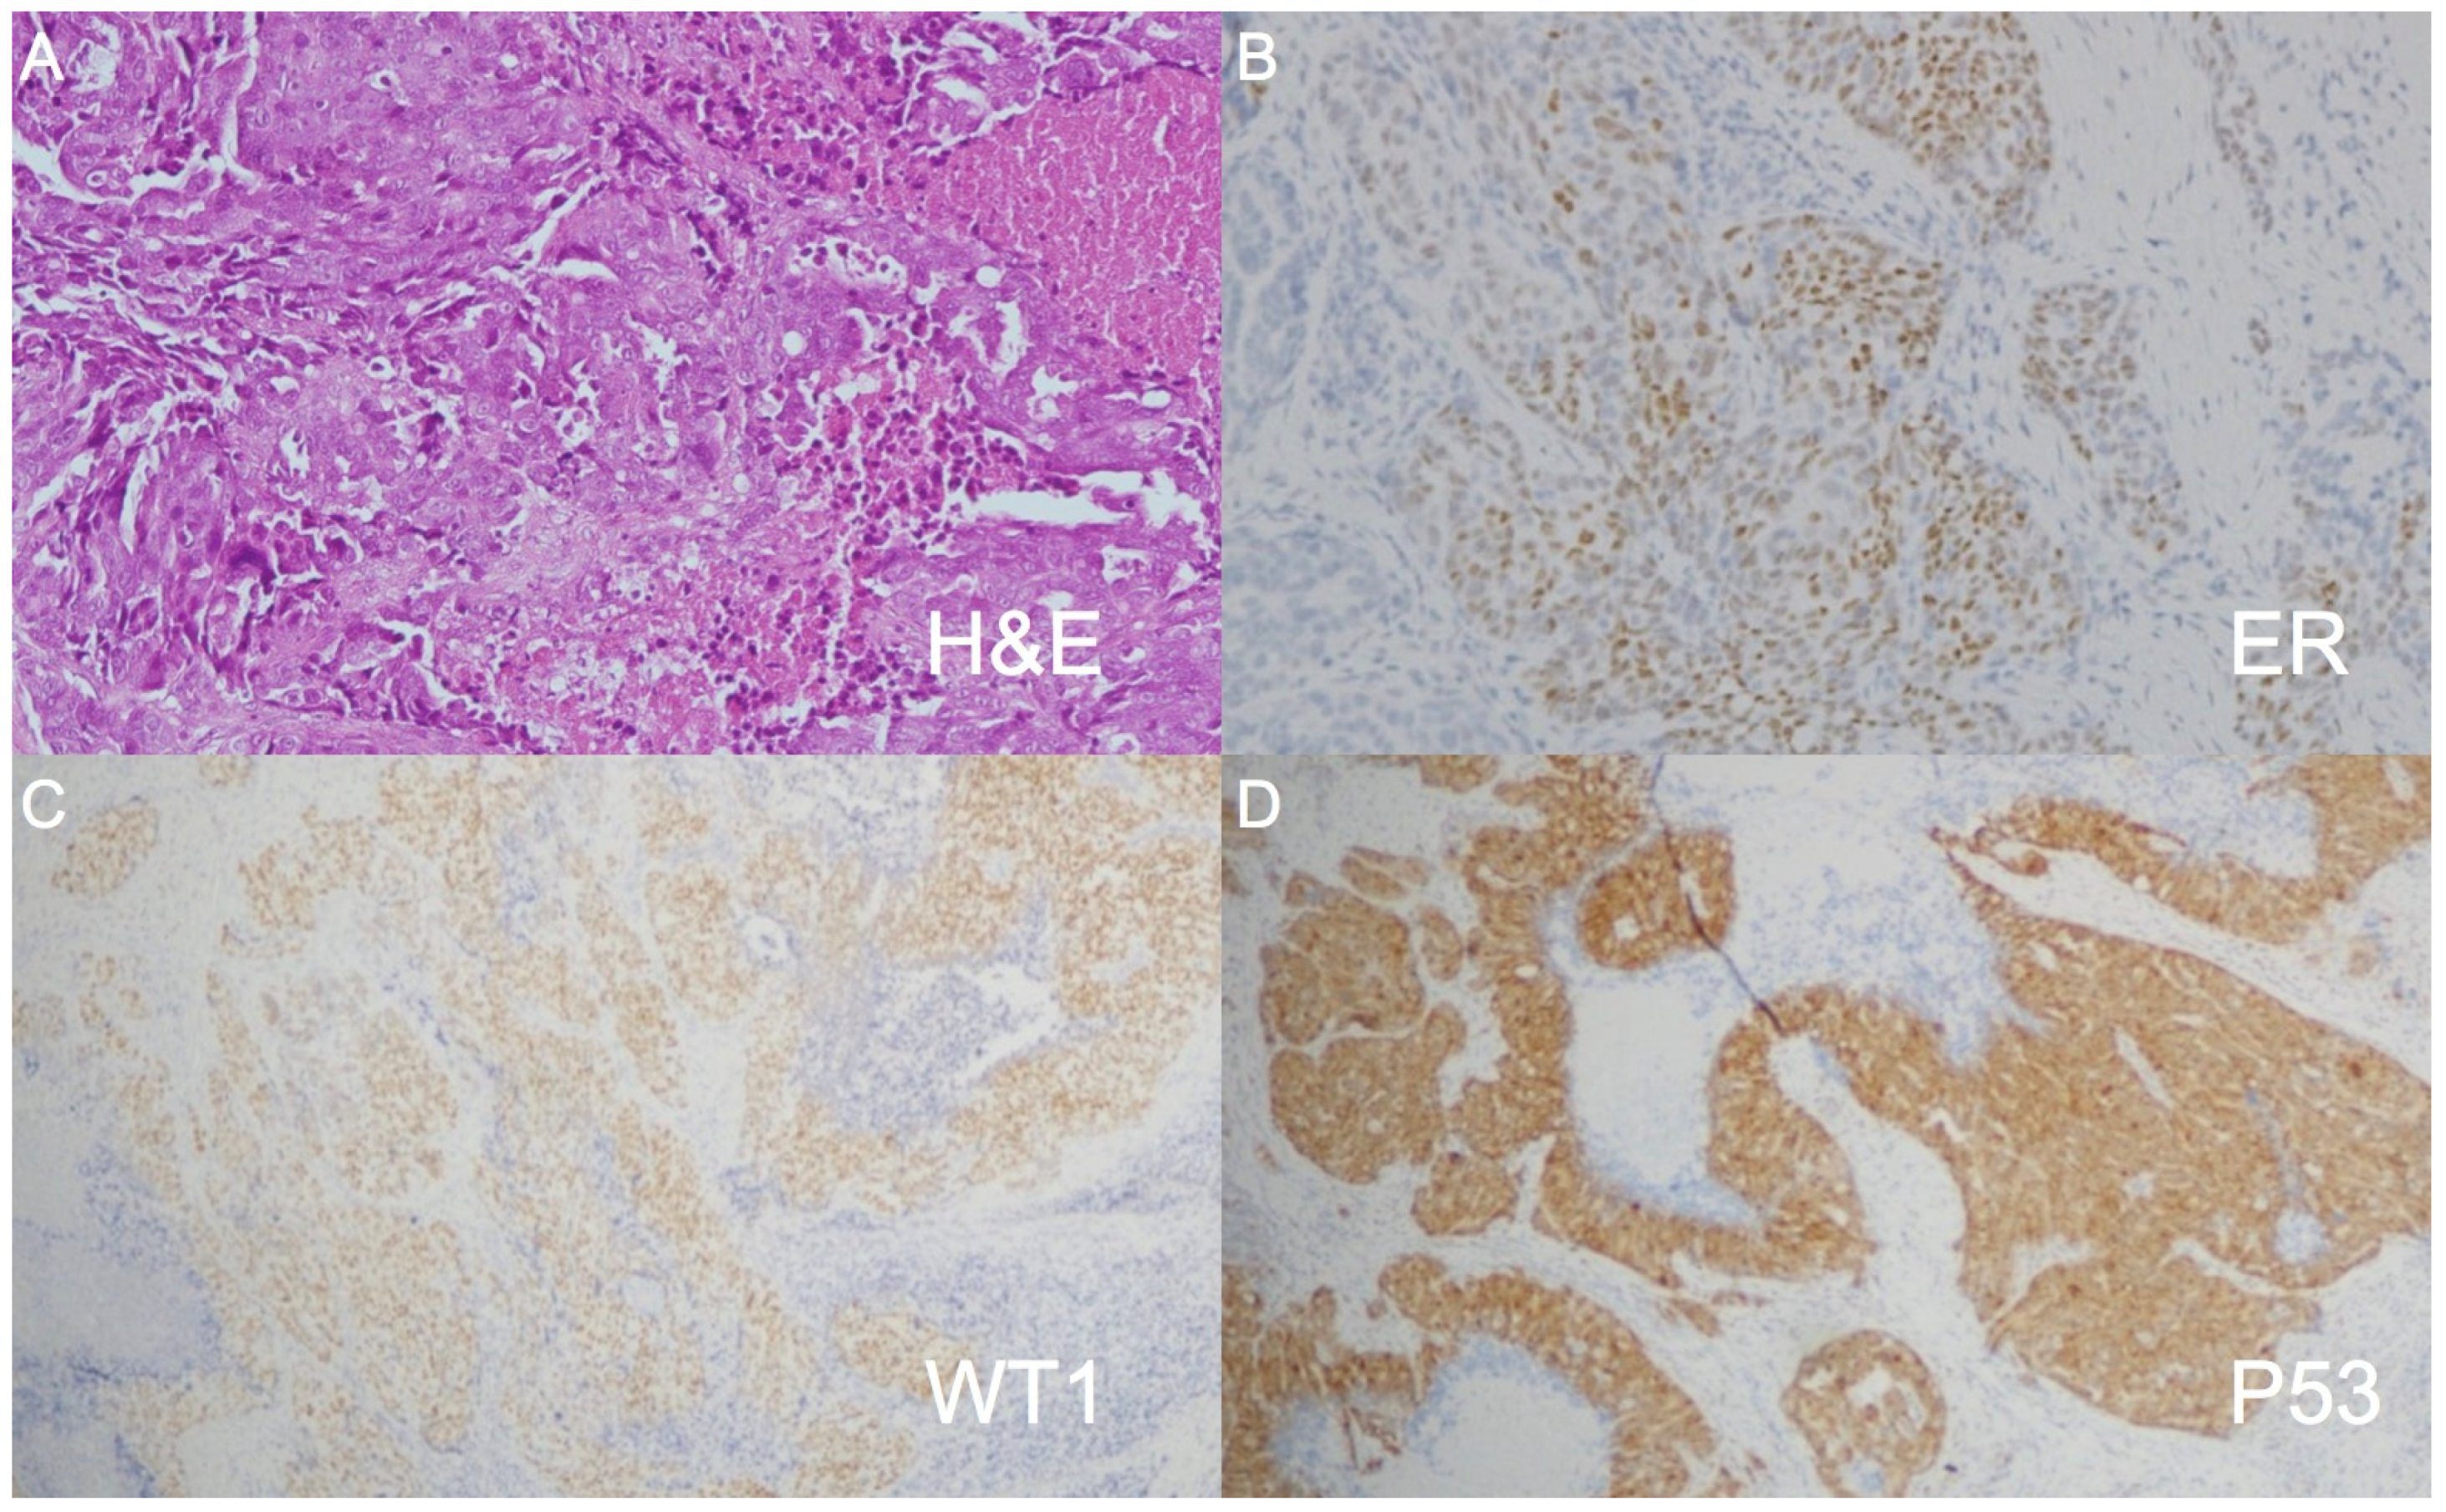

2. Case Report

3. Discussion